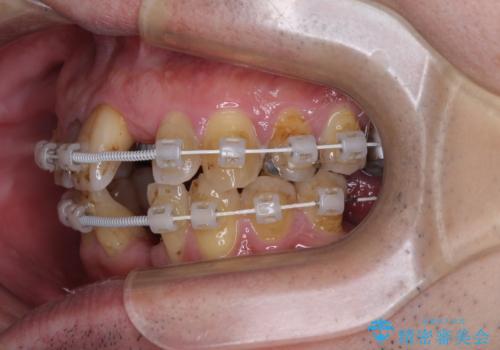

- むし歯治療途中で放置された歯が多く、スペースができたり歯が寄って来たりしているのを気にして来院された患者様です。

矯正治療を行いながら、欠損部はインプラントによる補綴治療を希望されたため、補助装置を用いたワイヤー矯正によりスペースを確保しながら歯列を整え、適宜インプラントを埋入していくこととしました。